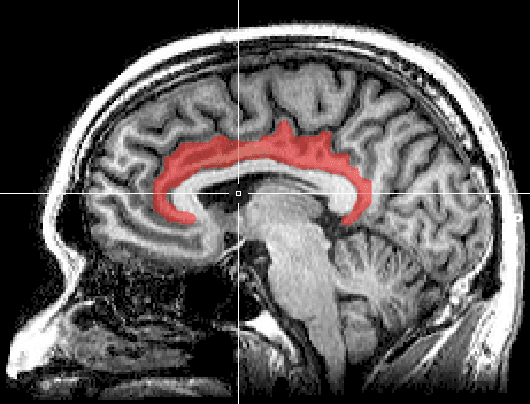

Le gyrus cingulaire est un gyrus du lobe limbique du cortex cérébral. Il est situé sur la face médiale des hémisphères, au-dessus du corps calleux. Au-dessus, il est séparé du gyrus frontal supérieur par le sillon cingulaire et du précuneus par le sillon sous-pariétal. En dessous, sa limite est le sillon du corps calleux. Au niveau du splénium du corps calleux, le gyrus cingulaire se rétrécit dans l'isthme qui se poursuit par le gyrus parahippocampique. En latin, cingulum signifie « ceinture » (Gaffiot). L'ensemble gyrus cingulaire, gyrus parahippocampique et diverses formations olfactives forment un anneau presque fermé qui s'appelle gyrus fornicatus (en latin, fornicatus signifie « voûté, cintré »). Le cortex cingulaire est une structure hétérogène, qui peut être divisée en plusieurs parties différentes quand on prend en compte la cytoarchitecture, les connexions et les fonctions. La division du cortex cingulaire en deux parties, l'antérieure et la postérieure, a été proposée par Korbinian Brodmann en 1909 sur la base d'une différence anatomique et en ignorant les fonctions de ces régions. Ce n'est qu'un siècle plus tard, grâce à la , que l'on commence à localiser les réponses fonctionnelles. Mais ces études ne permettent pas de tirer des conclusions sur les bases cytoarchitecturales des observations fonctionnelles et la division binaire de Brodmann continuant à être prise à la lettre, il en est résulté une profusion incohérente de dénominations des divisions Les deux divisions principales sont classiquement désignées : le cortex cingulaire antérieur CCA, qui consiste dans les aires de Brodmann 24 et 25, le cortex cingulaire postérieur CCP, qui consiste dans les aires de Brodman 29, 30, 23, et 31, assure des fonctions « évaluatives ». Parfois la région retrospleniale formée des aires 29 et 30 est considérée à part. Vogt (1993) a proposé une nouvelle division en quatre parties : le cortex cingulaire antérieur, CCA le cortex cingulaire moyen, CCM le cortex cingulaire retrosplenial, CRS le cortex cingulaire postérieur, CCP On peut diviser le gyrus cingulaire en quatre grandes parties, chacune d'elles accomplissant des tâches spécifiques.